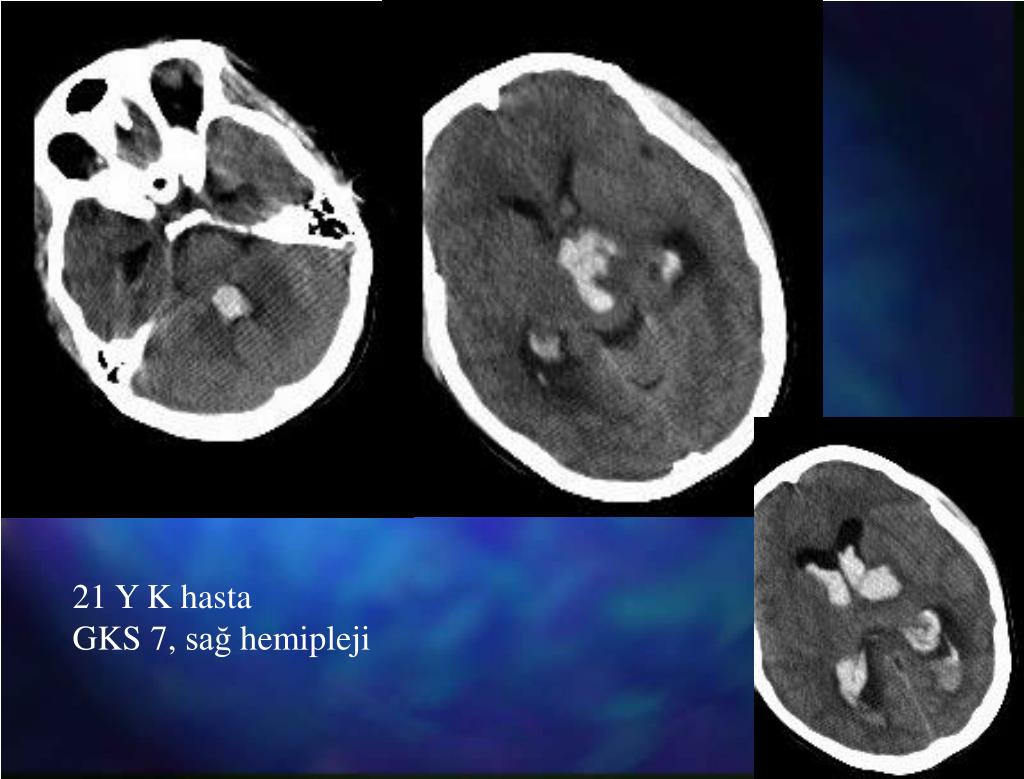

21. 21 Y K hasta GKS 7, sağhemipleji